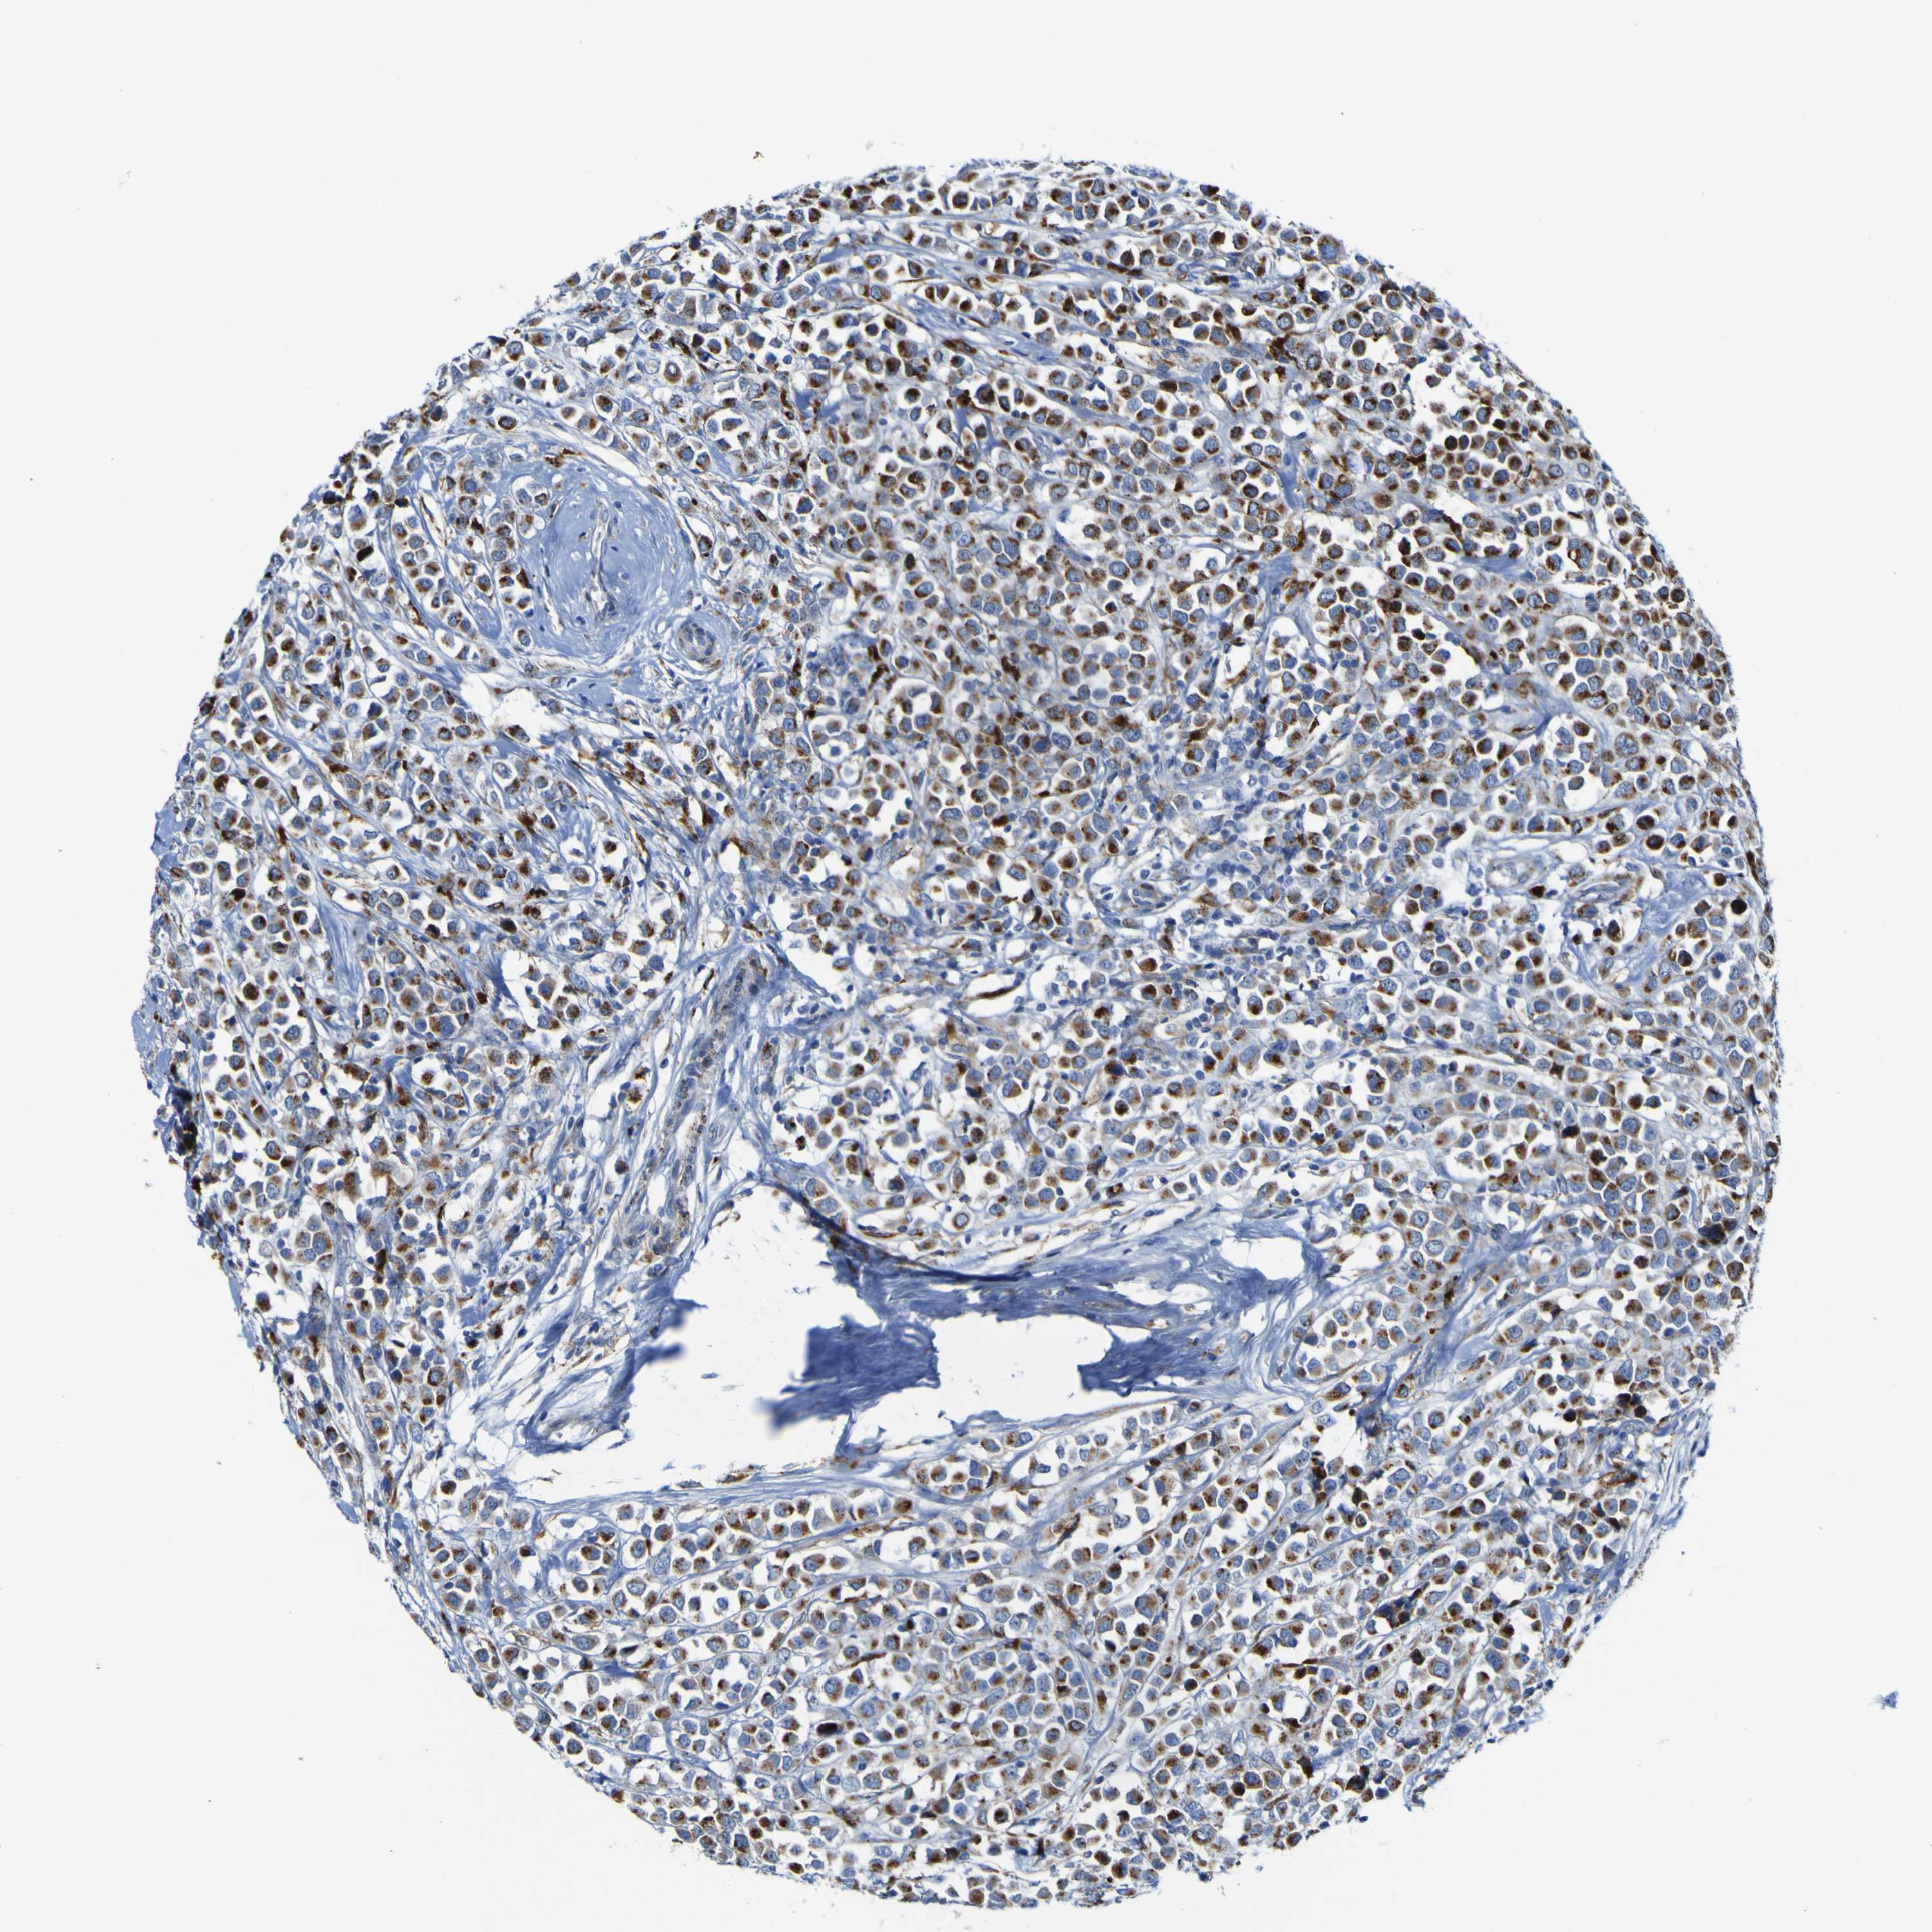

CANCER BREAST CANCER Show tissue menu

BRCA TCGA BRCA VALIDATION PROTEIN EXPRESSION